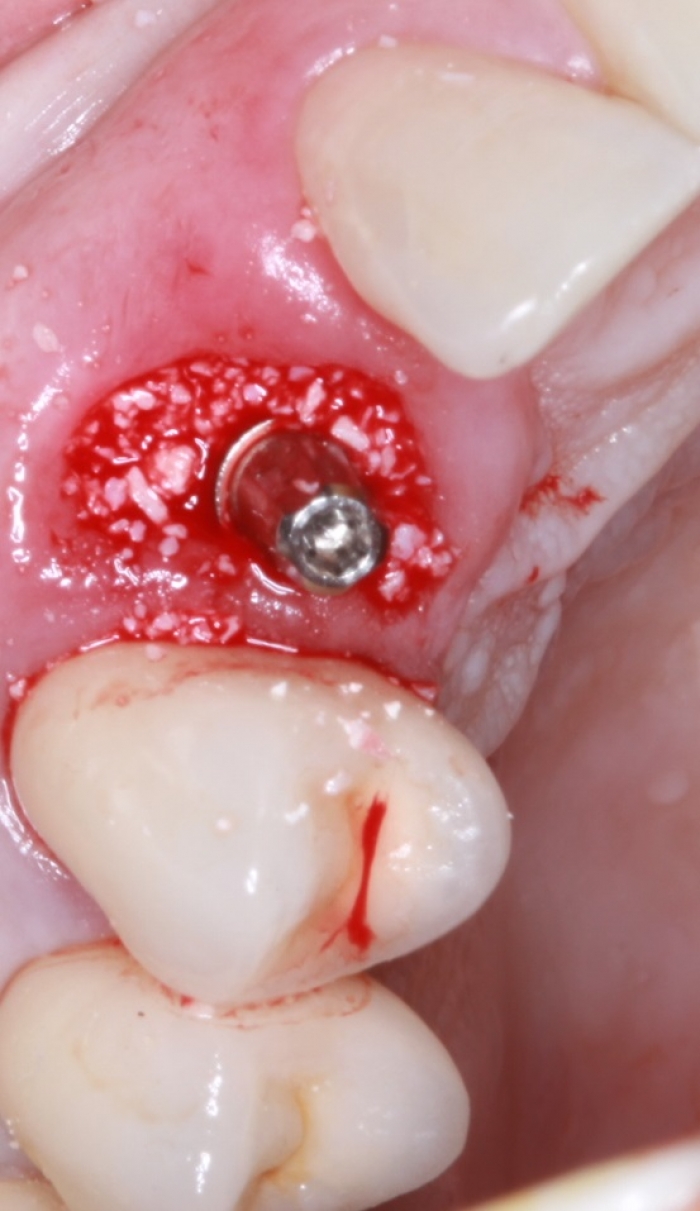

Foto implante   enxerto Bio Oss 03-10-16 - Clínica Cliniface

Foto implante enxerto Bio Oss 03-10-16